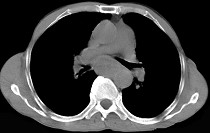

- 单项选择题女性患者,67岁进行性吞咽困难半年, X线及CT检查如图,应诊断为 ( )

A、食管癌

B、食管憩室

C、食管炎

D、食管良性狭窄

E、食管静脉曲张